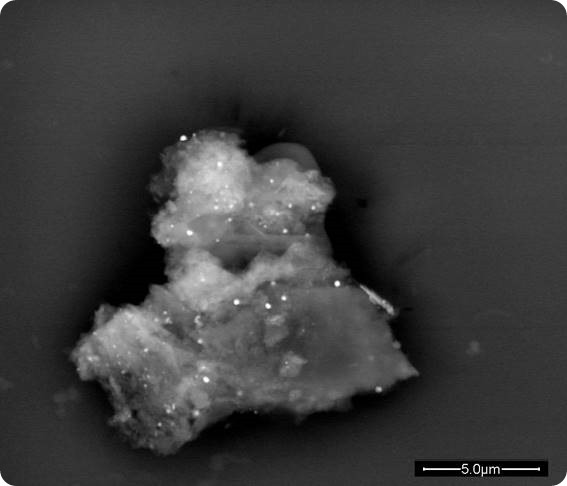

A proteic aggregate with embedded spherical nanoparticles. The formation is due to the nanobiointeraction.

In a way and in many cases, the simplest thing to do when you want to explore a territory is to become able to see it and Scanning Electron Microscopy allows you to see micro- and nanoparticles inside the pathological tissues and verify directly the interaction.

Optical microscopy is necessary to issue a diagnosis but is not appropriate and powerful enough to appreciate the details of what happens between particles and biological tissues. Scanning Electron Microscopy allows to see the shape of particles, their size and their arrangement in the tissue and even inside the cells, and allows to use a sensor of equipment called EDS (Energy Dispersive System) that can give you an accurate analysis of the elemental composition of the particles you are observing. All that information is essential to understand the phenomenon.

By having the diagnosis issued by the histopathologist available and the characterization of the particles you got though Scanning Electron Microscopy, you can start creating protocols to study the interactions you are interested to.